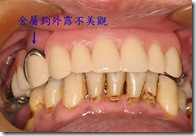

患者A先生

上顎 正面 下顎

患者B小姐

以上兩位患者口內狀況非常複雜,要制定一個好的治療計畫,

不只要考慮到患者的牙齒條件,

還要顧及患者意願、時間、金錢、評估可獲得的結果等等。

所以像這類型的Case 醫師通常在初步的溝通後會先做出一兩個不同的治療計畫,

再和患者解釋,了解患者接受程度。

(4)有時金屬物外露,美觀不良。